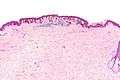

Low magnification

Intermediate magnification

Very high magnification